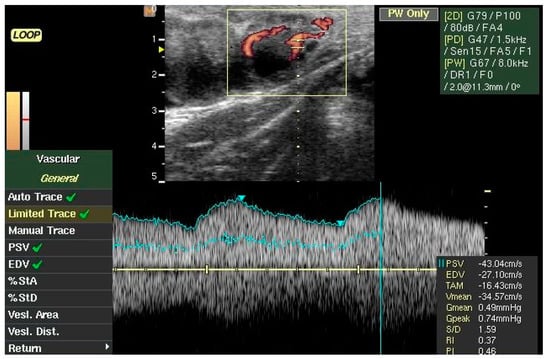

2.3. Corpus Luteum and Blood Flow Evaluation